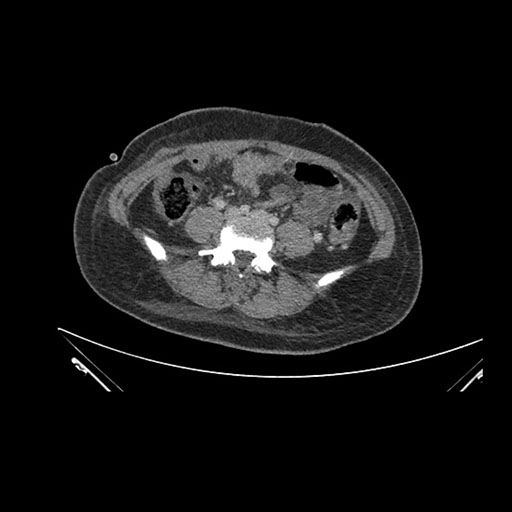

Imaging Analysis

Look through the patient's CT scan to identify any areas of concern for the necessary procedure.

Axial Arterial